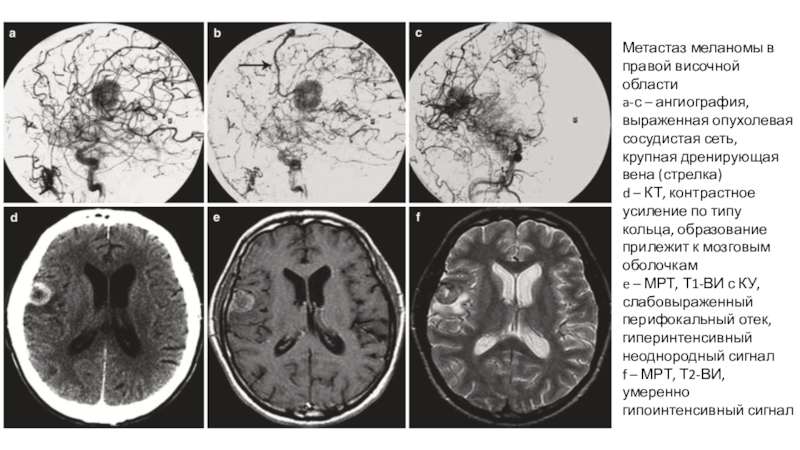

Слайд 25Метастаз меланомы в правой височной области

a-с – ангиография, выраженная опухолевая

сосудистая сеть, крупная дренирующая вена (стрелка)

d – КТ, контрастное усиление

по типу кольца, образование прилежит к мозговым оболочкам

e – МРТ, Т1-ВИ с КУ, слабовыраженный перифокальный отек, гиперинтенсивный неоднородный сигнал

f – МРТ, Т2-ВИ, умеренно гипоинтенсивный сигнал

Метастаз меланомы в правой височной областиa-с – ангиография, выраженная опухолевая сосудистая сеть, крупная дренирующая вена (стрелка)d –